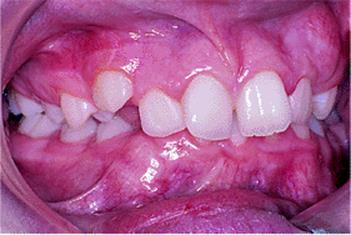

Fig. 10.3. Class II division 2 malocclusion with retroclination of all the upper incisors owing to a high lower lip line which is evident in the view of the patient smiling.

Fig. 10.4. Typical Class II division 2 malocclusion with retroclination of the upper central incisors. The lateral incisors, which are shorter, escape the effect of the lower lip and lie at an average inclination, albeit slightly mesiolabially rotated and crowded.